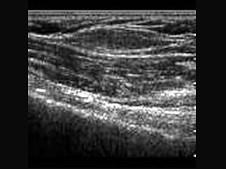

患者上肢可扪及一包块,质软、活动度差,加压可变形。如图,提示为?(?)A.脂肪瘤B.纤维瘤C.软组织局限增厚D.炎性包块E.以上均不是

问题 患者上肢可扪及一包块,质软、活动度差,加压可变形。如图,提示为?(?)

选项 A.脂肪瘤 B.纤维瘤 C.软组织局限增厚 D.炎性包块 E.以上均不是

答案 C